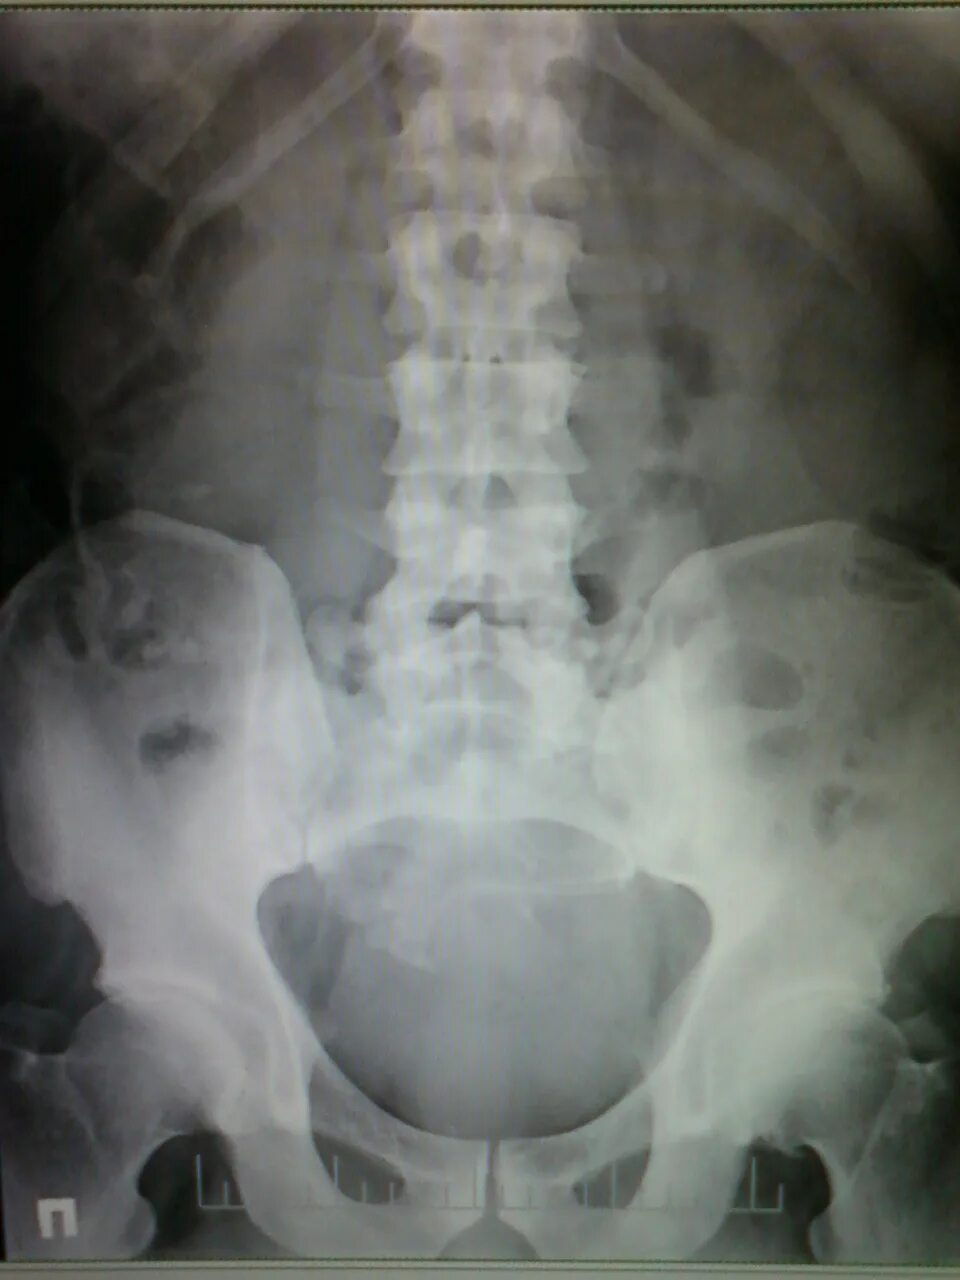

Снимок копчика